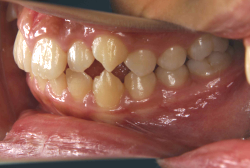

「出っ歯を治したい」という主訴で来院したケースです。診断の結果、「2級1類の上顎前突+軽度叢生」と判明しました。2級というのは、基本的に出っ歯の噛み合わせになっていることを言います。その中でも上の前歯が著しく外に反っているケースを、「1類」といいます。初診時の横向きの写真を見ると、それがはっきり分かります。上の前歯に押されて唇も膨らんで、審美線をかなりオーバーしています(審美線とは、鼻の先端と顎の先端を結ぶ線のことで、この線よりも唇は内側にある方が良いとされています)。

このような症状の場合は、前歯を内側に入れるためにかなり大量の隙間を必要とします。通常は上下左右の小臼歯を抜歯させていただくのが正解です。治療後は歯の角度が正しくなっただけでなく、唇の審美性が大幅に改善しました。もちろん噛み合わせ的にも正しい状態が確立しています。